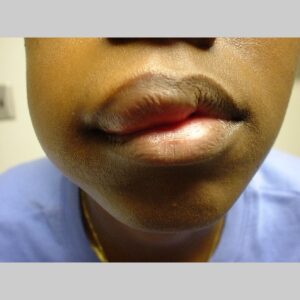

Angioedema is the swelling of deep dermis, subcutaneous or submucosal tissue due to vascular leakage.1 It was first described in 1586.2 Other terms, such as giant urticaria,3 Quincke edema,4 and angioneurotic edema,5 have also been used in the past to describe this condition. Clinically, angioedema is usually nonpitting and nonpruritic. The area of involvement is often skin-colored or slightly erythematous. Depending on the area of swelling, pain can be absent or mild, as in most peripheral or facial swelling, or can be very severe, as in gastrointestinal angioedema. Laryngeal swelling is life-threatening. It should be treated as a medical emergency.

Patients usually describe swelling of the face (eg, eyelids, lips), tongue, hands, and feet. It can be acute or chronic, and each episode of angioedema may last a few hours to a few days. A local burning sensation and pain can be observed without pronounced itchiness or local erythema. Abdominal pain can sometimes be the only presenting symptom of angioedema. Throat tightness, voice changes, and trouble breathing may indicate airway involvement.

For skin involvement, examination can easily identify areas of swelling with or without erythematous skin, often with ill-defined margins. Some cases of angioedema occur in patients with urticaria.